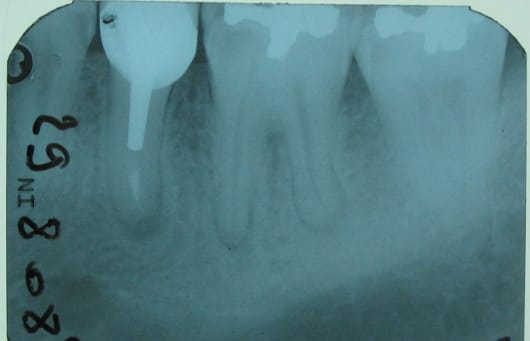

Une tâche laiteuse en mésial de 36,( dent asymptômatique),une radio pour confirmer la carie...

et je tombe sur des images apicales sur cette dent qui est vivante (sensible au test au froid mais nettement moins que la 37 ).

Ton image apicale est un épaississement ligamentaire. Cela ne veut pas dire qu'il y a nécrose pulpaire. La radio n'est pas prise selon un incidence bien orthogonale : on ne voit pas très bien cette lésion mésiale. Pour mieux évaluer son volume, une bite wing serait intéressante.

36 a déjà un Hg ayant entrainé semble t'il une retraction pulpaire( cf chambre)

en prime reprise de carie mesiale proche de la corne(et comme disait je ne sais plus quel prof d'endo : Santoro? :la radio est tjours en retard sur la clinique...)

la racine distale commence à présenter un aspect caractéristique"en battant de cloche"

mme la zone interradiculaire n'est pas clean...

Je penche aussi pour le TR, tu peux avoir 1 racine en nécrose et les 2 autres vivantes.